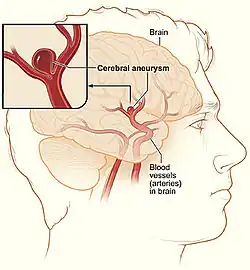

A cerebral aneurysm, also known as a brain aneurysm, is when there is a localized ballooning of a blood vessel located around the brain.[2][1] In most cases no symptoms are present.[2] Occasionally there may be numbness, pain, or an inability to move one side of the face.[1] Complications can include a subarachnoid bleed, which presents with a sudden onset of a severe headache.[2]

Aneurysm means an outpouching of a blood vessel wall that is filled with blood. Aneurysms occur at a point of weakness in the vessel wall. This can be because of acquired disease or hereditary factors. The repeated trauma of blood flow against the vessel wall presses against the point of weakness and causes the aneurysm to enlarge.[14] As described by the Law of Young-Laplace, the increasing area increases tension against the aneurysmal walls, leading to enlargement.